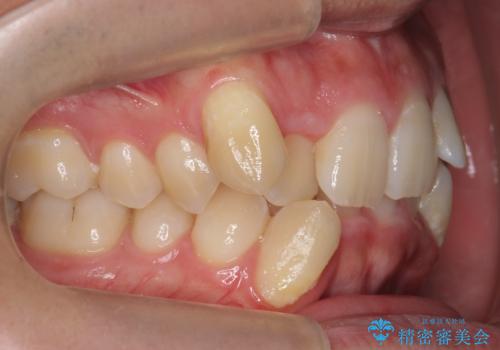

前歯のがたつき 下の八重歯

- 前歯のがたつきを主訴に来院。

上下の前歯の重なりが大きく(過蓋咬合)時間がかかりましたが、しっかり浅く仕上げることができました。

矯正をしてよかったと大変喜んでおられました。